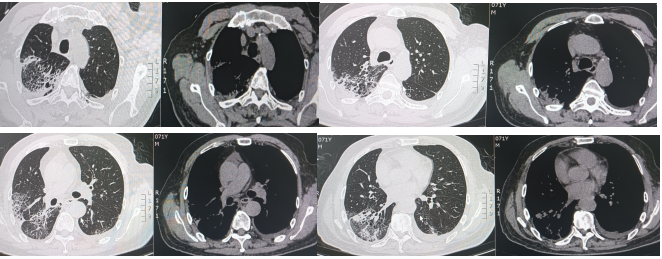

入院后给予奈诺沙星0.5 g qd ivgtt、头孢他啶阿维巴坦2.5 g q8h ivgtt经验性抗感染治疗。治疗5天后复查相关指标:白细胞计数9.69×109/L,中性粒细胞绝对数7.31×109/L,C反应蛋白90.4 mg/ml,血清淀粉样蛋白>288.00 mg/L,红细胞沉降率测定94 mm/h;胸部CT:右肺上叶、下叶间质性炎症,左下肺小结节,炎性结节可能(图2)。提示病变无明显好转,告知家属病情后再次行气管镜检查,行病原学检查及病理检查,结果示:BALF涂片、培养、GM均阴性;BALF NGS回报:流感嗜血杆菌、烟曲霉。冷冻肺活检病理:(右肺下叶后基底段)肺组织急、慢性炎,肺泡腔内见纤维素样渗出物伴泡沫细胞聚集。免疫组化结果:CK7(+),TTF1(+),SMA(平滑肌+),NapsinA(+),PGM-1(+),Ki-67(+, 5%),P40(+),CD68(+)。考虑真菌感染不除外于8月31日加用伏立康唑0.2 g q12h ivgtt;醋酸卡泊芬净70 mg qd ivgtt抗真菌对症治疗。图2 2024年8月27日复查胸部CT较8月21日胸部CT无明显吸收9月5日再次复查相关指标:白细胞计数12.38×109/L,中性粒细胞绝对数9.27×109/L,C反应蛋白151.46 mg/ml,血清淀粉样蛋白>288.00 mg/L,红细胞沉降率117 mm/h。胸部CT:右肺散在间质性炎症,左下肺新发炎症灶,较前进展,左下肺小结节,范围较前增大(图3)。图3 2024年9月5日胸部CT右下肺炎症较8月27日进展,左肺出现新发炎症灶9月5日行MDT讨论,考虑感染继发机化性肺炎不除外,建议在目前抗感染治疗保驾下予中等剂量激素治疗,并严密动态观察相关指标。9月6日起治疗上加用甲泼尼龙琥珀酸钠80 mg qd ivgtt。治疗1周后(9月12日)复查相关指标:复查炎症标志物:白细胞计数16.47×109/L,中性粒细胞绝对数14.79×109/L,C反应蛋白11.08 mg/ml,血清淀粉样蛋白25.388 mg/L,红细胞沉降率28 mm/h。胸部CT:双肺散在间质性炎症(右肺为著),较前吸收(图4)。9月12日调整激素剂量为醋酸泼尼松片35 mg qd口服;9月19日患者无发热,无明显咳嗽、咳痰不适,予出院并嘱出院后维持醋酸泼尼松片35 mg qd口服,1周后每周减5 mg,减至20 mg后维持1周并复查胸部CT,根据胸部CT结果调整剂量。10月21日患者门诊复查胸部(图5),较前明显吸收,激素调整为醋酸泼尼松片10 mg qd,目前在持续随访中。治疗期间感染相关指标变化情况如图6所示。机化性肺炎(organizing pneumonia,OP)是一种肺组织修复过程,是以肺泡腔/管内有息肉状肉芽组织为病理特点,主要由成纤维细胞、肌成纤维细胞和疏松结缔组织基质构成[1]。同时与其他肺损害,如血管炎、淋巴瘤、肺癌、过敏性肺炎(hypersensitivity pneumonitis,HP)、嗜酸性粒细胞性肺炎(eosinophilic pneumonia,EP)、急性间质性肺炎(acute interstitial pneumonia,AIP)、非特异性间质性肺炎(nonspecific interstitial pneumonia,NSIP)或普通型间质性肺炎(usual interstitial pneumonia,UIP)关系密切。OP具有复杂的多态性,具有急性、亚急性和慢性多种形式。OP可以根据病因分为隐源性机化性肺炎(cryptogenic organizing pneumonia,COP)和继发性机化性肺炎(secondary organizing pneumonia,SOP)。COP与SOP在临床表现、影像表现和肺功能无明显差异[2],当有相关病因时诊断为SOP,当临床未发现相关潜在疾病时诊断为COP。OP的概念最早在肺炎链球菌的大叶性肺炎中被阐述,OP的发病机制目前主要认为肺泡上皮损伤,纤维蛋白渗出,导致成纤维细胞增生-肌成纤维细胞增生[3]。机化存在于多种肺损伤中,具有相同的本质,无论是局灶性还是弥漫性肺损伤,以成纤维细胞增殖为特征的机化是一种常见且几乎普遍的反应[4],机化被认为是对炎症渗出的反应和局限,很可能代表疾病的一个阶段,而不是独立的疾病。所以如果有确认感染的证据,虽然CT上发现有机化的特征,临床诊断OP往往是不必要的,除非这种机化是主要表现,而且改变了疾病进程。因此关注整体,将OP作为疾病的一个阶段,有利于建立对疾病的全息认识。OP没有特异的临床特征,患者可能出现发热、咳嗽、乏力、轻度呼吸困难、厌食症和体重减轻等,类似于流感[5],临床表现不特异。有些患者接受经验性抗生素治疗后往往无效,且疾病可能会迅速进展,导致严重的呼吸困难,甚至是ARDS,往往存在延误诊断。有文献报道大部分OP患者为不吸烟患者,肺功能主要表现为限制性通气障碍,也可表现为混合型和阻塞性通气障碍[6]。也有学者研究SOP患者有胸腔积液,而COP患者未报告胸腔积液[7]。因此,胸腔积液似乎与背景疾病有关,而与OP本身无关。OP的CT表现可以按照发生率分为典型和非典型模式[6],多数患者表现为典型模式,即多灶性实变,常被描述为斑片状肺泡阴影,一般位于下肺外周或支气管血管周围;实变可伴有支气管充气征,并可伴有散在的磨玻璃病变或小结节。而非典型的病变表现多样,可为磨玻璃影,也可为结节或肿块样表现、反晕征、铺路石征、小叶周围病变、线性和带状阴影以及网状结构。OP虽然有多种影像学表现,但均不特异,类似的表现同样可以出现在其他疾病中。例如,迁移性病灶可提示嗜酸性粒细胞性肺炎、感染、血管炎和复发性出血[8];弥漫性微小结节可见于过敏性肺炎、细支气管感染和炎症;反晕征可见于多种感染、非感染性肉芽肿异常,甚至原位腺癌[9]。因此诊断OP不能单纯依靠CT,需要结合临床和病理特征。目前针对OP的治疗,COP主要是以糖皮质激素为主[10],SOP需要兼顾原发疾病治疗及激素应用,因此我们需要尽早明确病理,及时治疗,减少不良预后。针对重症患者,尽早获取病理是必要的。此病例我们初步诊断为CAP,予抗感染治疗后疾病进展,及时行二次支气管镜冷冻肺活检+灌洗,同时通过mNGS及病理检查,最终被诊断为SOP,经激素抗炎治疗后症状好转,影像学提示病灶明显吸收。总之,OP在临床上并不少见,但由于其临床表现无特异性且CT表现多样,所以及时正确诊断OP罕见,诊断OP需要结合临床和病理特征,只有当OP成为主导性特征且干扰了疾病进程,才被冠以OP的诊断。针对初诊为肺炎的患者,当经验性抗感染治疗效果欠佳时,需要及时明确病原学检查及病理诊断,及时修改诊断及治疗路径,及时干预[11]。[1] CottinV,CordierJF. Cryptogenic organizing pneumonia[J]. Semin Respir Crit Care Med, 2012, 33(5): 462-475.